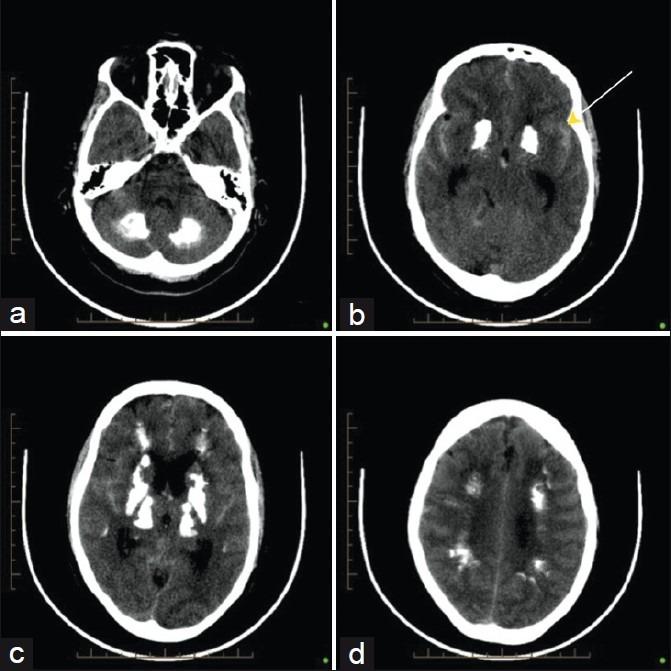

Fahr's disease is a rare disorder of slowly progressive cognitive, psychiatric, and motor decline associated with idiopathic basal ganglia calcification (IBGC) and widespread calcification in the brain and cerebellum. Acute presentation of IBGC is most often as a seizure disorder; however, we present a case of an acute IBCG presentation in which the cause of the deterioration was an aneurysmal subarachnoid hemorrhage.

法尔氏病是一种罕见的疾病,其特征为认知、精神和运动功能缓慢进行性衰退,与特发性基底节钙化(IBGC)以及大脑和小脑的广泛钙化有关。IBGC的急性表现最常见的是癫痫发作;然而,我们报告了一例急性IBCG表现的病例,其病情恶化的原因是动脉瘤性蛛网膜下腔出血。